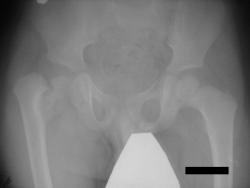

Нет, травмы в данном случае не было. Имеет место дистрофическая coxa vara, вероятнее всего, врождённаяю. Эпифизеолиз головки, который мы видим на снимке, как мы считаем, наступил вследствие нарушений биомеханики в суставе - ШДУ практически 90 градусов. Добавлю, что факт травмы родители категорически отрицают. Ребёнок постепенно начал хромать, хромата усиливалась на протяжении 6 месяцев.

P.s. Сегодня этого ребёнка мы прооперировали.